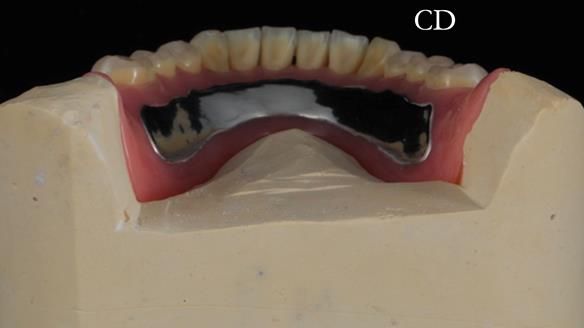

The detailed clinical situation and treatment process are outlined below, with clinical work provided by me and technical work by Rowan Garstang. The treatment spanned 12 months, involving removing 5 upper anterior teeth, adding to an existing upper RPD, followed by creating and fitting metal based complete dentures.